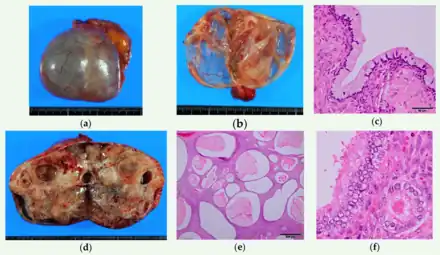

Mature cystic teratoma (MCT), affecting women in 10–20% of cases during their lifetime, is characterized by benign mature cystic teratomas—an intriguing subject in gynecological pathology.[8][3] These non-cancerous tumors, originating from at least two embryonic germ cell layers, exhibit a complex interplay of developmental pathways, stemming from singular germ cells or the complexities of meiosis I and II failure.[9][10] Internally lined with squamous epithelium and externally connected to the ovarian stroma, mature cystic teratomas contain diverse fluids such as sebaceous, serous, or mucinous.

Although the majority of MCT cases are non-malignant, approximately 0.17-2% may undergo malignant transformation, with squamous cell carcinoma being the most prevalent, constituting 80% of such transformations.[11] The clinical presentation of oSCC development within MCT lacks specificity, often resulting in the inadvertent discovery of early-stage tumors during routine examinations or postoperative assessments. In advanced cases, patients may exhibit palpable masses, abdominal swelling, and pain, potentially leading to acute abdominal complications due to tumor involvement.[10][12][4]

Pathologic examination of biopsies helps distinguish between benign and malignant lesions, aiding in the identification of different cancer types. Larger excisional specimens, known as resections, provide comprehensive information about the cancer, its sub classification, histologic grading, and the extent of its spread, contributing to the pathologic staging. In cases where visible growth[22] or malignant transformation is not apparent,[23] a precise grossing and thorough histopathological examination are essential for an accurate diagnosis. Additionally, conducting situ hybridization for HPV DNA is crucial to rule out the potential involvement of papillomavirus in this condition. To distinguish between primary ovarian serous carcinoma (OSC) and metastatic squamous cell carcinoma (SCC), various immunohistochemical markers such as PAX8, p16, WT1, ER, p53, and CK5/6 are utilized.[23] The p53/p16 index was recognized as a valuable indicator for high-grade OSC, demonstrating diffuse p53 expression or complete absence (null type) along with diffuse p16 expression.[23]